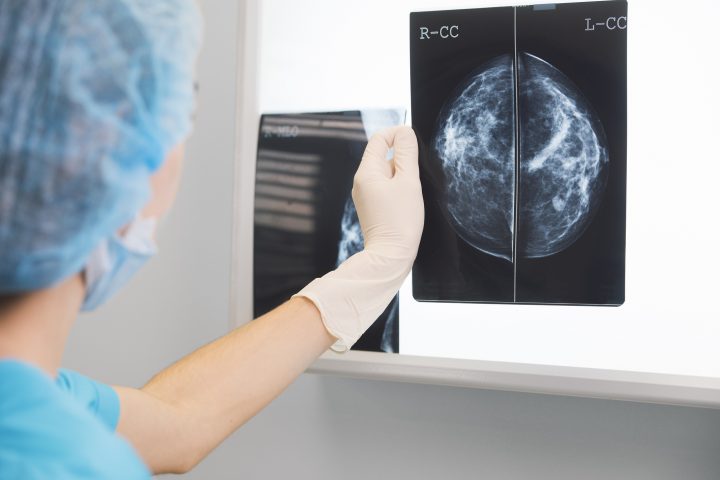

Minsal incorpora la primera inmunoterapia contra el cáncer de mama triple negativo